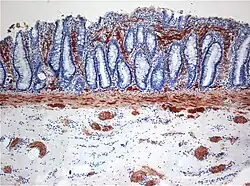

Histopathology of Hirschsprung disease showing abnormal acetylcholine esterase (AchE)-positive nerve fibers (brown) in the mucosa

Definitive diagnosis is made by suction biopsy of the distally narrowed segment.[30] A histologic examination of the tissue would show a lack of ganglionic nerve cells. Diagnostic techniques involve anorectal manometry,[31] barium enema, and rectal biopsy. The suction rectal biopsy is considered the current international gold standard in the diagnosis of Hirschsprung's disease.[32]